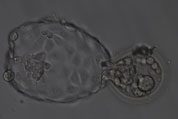

The oocytes that have been removed from the ovary of the woman are placed in a Petri dish with her partner’s sperm. The oocytes (eggs) are later checked to see if they have fertilized and made zygotes (embryos).

The embryos are cultured for six days. The growth pattern is carefully followed. This allows us to pick the best embryos to be placed in the uterus. The physicians will inform the patients of the best time to replace the embryos.

Embryo transfer is done on day 2, day 3 or day 5 of embryo culture. Our physicians follow strict guidelines laid down by SART and ASRM when deciding the number of embryos that are replaced.

Any embryos that remain in culture after the best embryos have been placed in the uterus are cultured till day 6 and frozen through a slow cooling method. This is called cryopreservation of embryos. These embryos can be thawed at a later stage and transferred to the patient’s uterus in a frozen embryo transfer.